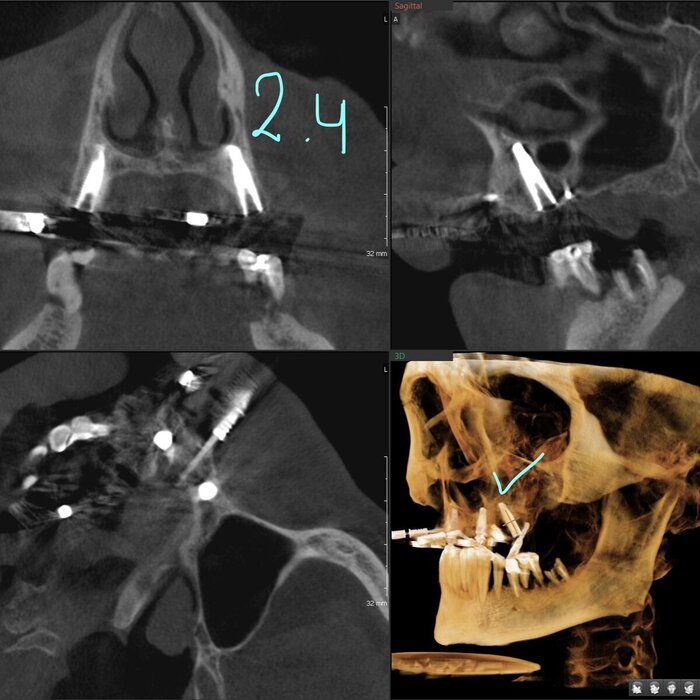

Примерка временного протеза "всё на 4-х"

Постановка на воске.

Временный протез "всё на 4-х", постановка на воске